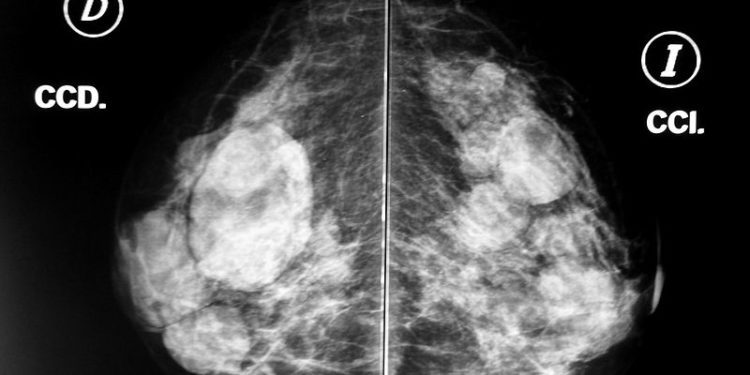

En estos momentos, la dirección general de Salud Pública de Baleares coordina dos programas de cribados poblacionales para detectar de forma precoz los cánceres de mama y de colon y recto entre la ciudadanía en general mediante mamografías y pruebas de sangre oculta en heces, respectivamente. Salud Pública está ultimando asimismo la implantación de un nuevo programa para la detección precoz del cáncer de cuello uterino mediante pruebas de citología vaginal y detección del virus del papiloma humano (VPH) responsable de esta patología.

La conselleria de Salud insta a la población a participar en ellos como una de las mejores medidas de prevención recordando que el programa de detección precoz de cáncer de mama está dirigido a la población femenina con edades comprendidas entre los 50 y los 69 años, que es invitada a participar en él mediante un sms.

La prueba de cribado es una mamografía. Si no hay indicios de malignidad, se vuelve a citar a la mujer en dos años. En cambio, si la prueba diagnóstica requiere estudios posteriores, la paciente es derivada al servicio de radiología de su hospital de referencia para una valoración complementaria. En 2024 se invitaron a participar en el programa a 38.538 mujeres empadronadas en las Illes Balears, de las cuales 25.588 tuvieron mamografías normales y 1.280 mujeres fueron derivadas a estudios mamográficos complementarios.